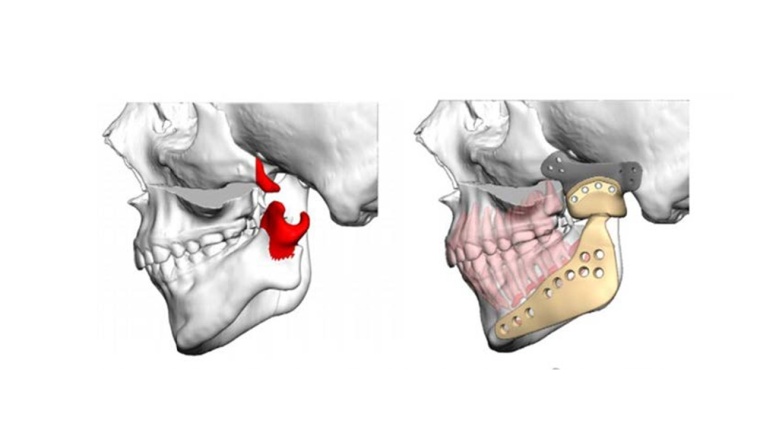

Fokussierte sich klassisch die Behandlung von dentalen und skelettalen Fehlstellungen im Rahmen der Behandlung der Patienten mit Goldenhar-Symptomkomplex auf das Wiederherstellen z. B. des betroffenen aufsteigenden Unterkieferastes, der Okklusion oder der Auffüllung des Mittelgesichtes, so kann anhand des vorzustellenden Fallbeispiels das modernste Zusammenspiel von virtueller OP-Planung, CAD/CAM-Implantaterstellung und zielgenauer einzeitiger Umsetzung dargestellt werden, d. h. einzeitiger Ausgleich der schrägstehenden Okklusionsebene, der ausgeprägten Gesichtsskoliose (konvex zur Gegenseite der bestehenden Deformität), Retrogenie, Fehlen der Untergesichtsweite und – höhe auf der betroffenen Seite.

Anhand einer virtuellen Planung und Computerassistierten Behandlung werden bei einer jungen Erwachsenen mit Goldenhar-Symptomenkomplex die Elemente von moderner computerassistierter Planung mit virtueller Blaupausenerstellung für das Operationsergebnis in Verbindung mit der digitalen Dysgnathieplanung als Planungsgrundlage für eine Wiederherstellungsoperation bei angeborener Gesichtsschädeldeformität dargestellt; verknüpft wird dieses Rekonstruktionsbeispiel zudem mit erweiterten Total Joint Replacement, das digital geplant und gefertigt wurde.

Aus der jetzigen Konturbetrachtung der Hartgewebestrukturen von Corpus mandibulae, Kinnprojektion, Kieferwinkel und Anteilen des aufsteigenden Astes kann ggf. die Notwendigkeit eines Ersatzes, der betroffenen Kiefergelenkregion durch ein Total Joint Replacement notwendig werden. Es bedarf einer Gelenkpfannen-Komponente, die im Hinblick auf die deformierte Schädelbasissituation individuell angepasst sein muss und ggf. auch fehlende Jochbogenanteile – wie in diesem Fall - simultan mit ersetzt. Für die spätere Verankerung sind sowohl die chirurgisch vorbereitenden Maßnahmen zur Schädelbasis und auch die Bohrvorgänge und Schraubeninsertionen zu Verankerungen der Pfannen-Komponente durch Real-Time-Navigation unbedingt zu unterstützen. So lassen sich bei den deformierten Weich- und Hartgewebesituationen sicher die knöchernen Verankerungsmöglichkeiten nachvollziehen und chirurgisch umsetzen, und auch wichtige anatomische Strukturen, wie z. B. die großen Gefäße an der Schädelbasis, können geschont werden. Das skelettale Delta zur Schädelbasis im Bereich des aufsteigenden Astes, im Bereich des Kieferwinkels und des betroffenen Unterkieferkörpers mit insbesondere der Projektion nach unten und seitlich bis einschließlich zur Kinnregion, lässt sich nunmehr in das Design des Implantates für den patientenspezifischen Gelenkersatz integrieren. Hier wird durch biomedizintechnische Innovationen aufgrund von Computer-Assistenz und modernsten digitalen Planungs- und Fertigungstechniken deutlich, wie sich für die Patienten mit schweren angeborenen Fehlbildungen aus einer sonst langdauernden und viele Operationen umfassenden Behandlung eine drastische Therapieverbesserung erzielen lässt.